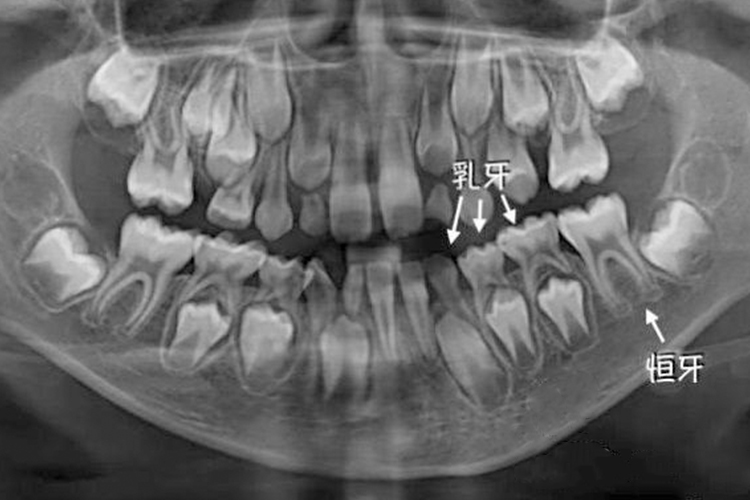

换牙期一般是指乳牙脱落,恒牙长出的过程,这个过程可能发生在6岁到12岁,但具体的时间会根据孩子的发育情况有所差异。

- 大多数孩子在6岁左右开始换牙,这时下颌的乳中切牙(即门牙)会首先脱落,随后恒牙开始萌出。换牙的顺序通常是先下后上,左右对称。具体来说,先换下中切牙,然后是上中切牙,接着是侧切牙、尖牙、第一磨牙、第二磨牙等,直到12岁左右时,所有的乳牙都会被恒牙替换完毕。